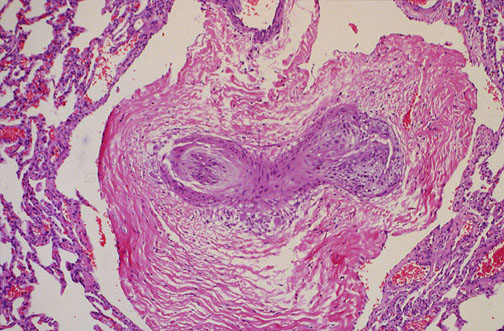

Ryc. 4 Wyraźna przebudowa naczynia tętniczego wyrażona do tego stopnia, że jego światło przestało być dostrzegalne. Obecność takich zmian sugeruje obecność utrwalonego nadciśnienia płucnego, co znacząco pogarsza rokowanie.